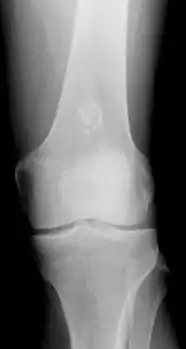

Diagnosistic tests include medical imaging.[2] Appearances on X-ray show a small lobe-shaped, dark tumor in the middle of the bone.[2] It typically contains white spots; calcified chondroid matrix (a "rings and arcs" pattern of calcification).[2] It does not extend into soft tissues.[6] Magnetic resonance imaging (MRI) and CT scan may be requested to further evaluate the tumor.[8]

X-ray: Solitary enchondroma in long bone of thigh near knee